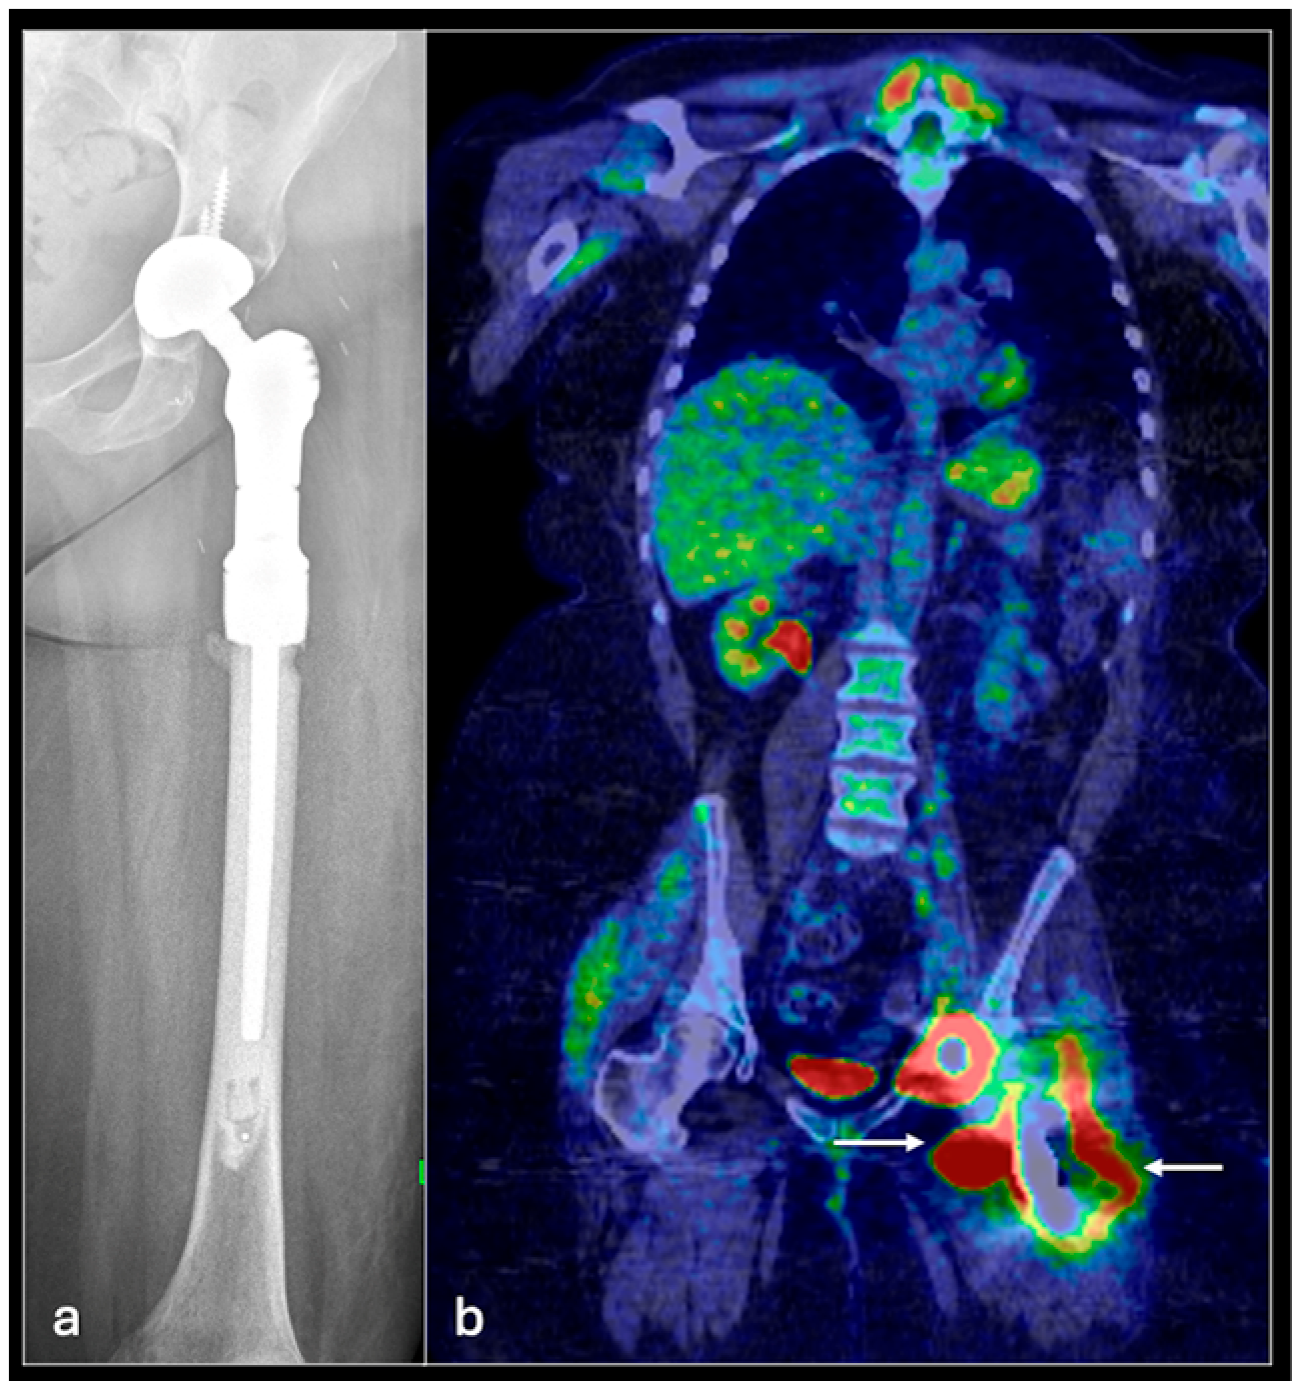

4.1. Osteosarcoma